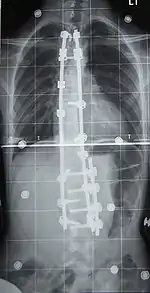

Surgery

Surgery is usually recommended by orthopedists for curves with a high likelihood of progression (i.e., greater than 45 to 50° of magnitude), curves that would be cosmetically unacceptable as an adult, curves in people with spina bifida and cerebral palsy that interfere with sitting and care, and curves that affect physiological functions such as breathing.[51]

Surgeons who are specialized in spine surgery perform surgery for scoliosis. To completely straighten a scoliotic spine is usually impossible, but for the most part, significant corrections are achieved.[53]

The two main types of surgery are:

- Anterior fusion: This surgical approach is through an incision at the side of the chest wall.

- Posterior fusion: This surgical approach is through an incision on the back and involves the use of metal instrumentation to correct the curve.

One or both of these surgical procedures may be needed. The surgery may be done in one or two stages and, on average, takes four to eight hours.